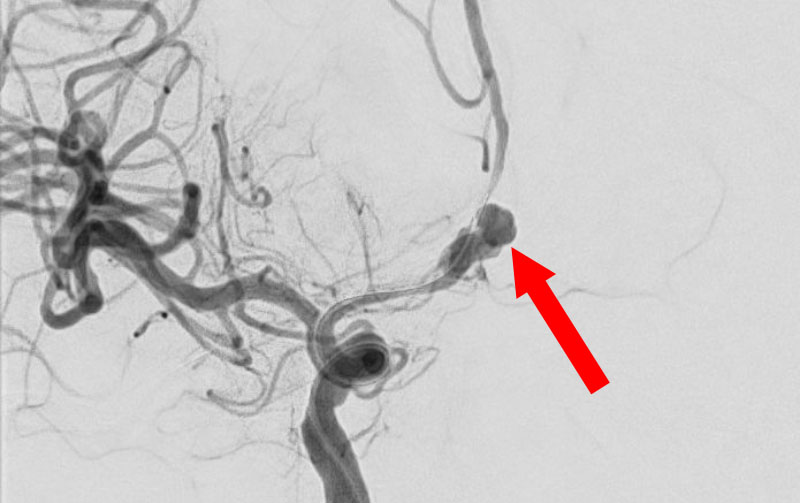

'25年10月

くも膜下出血

前交通動脈瘤破裂

40代

大阪府の病院

No.1589 手術前